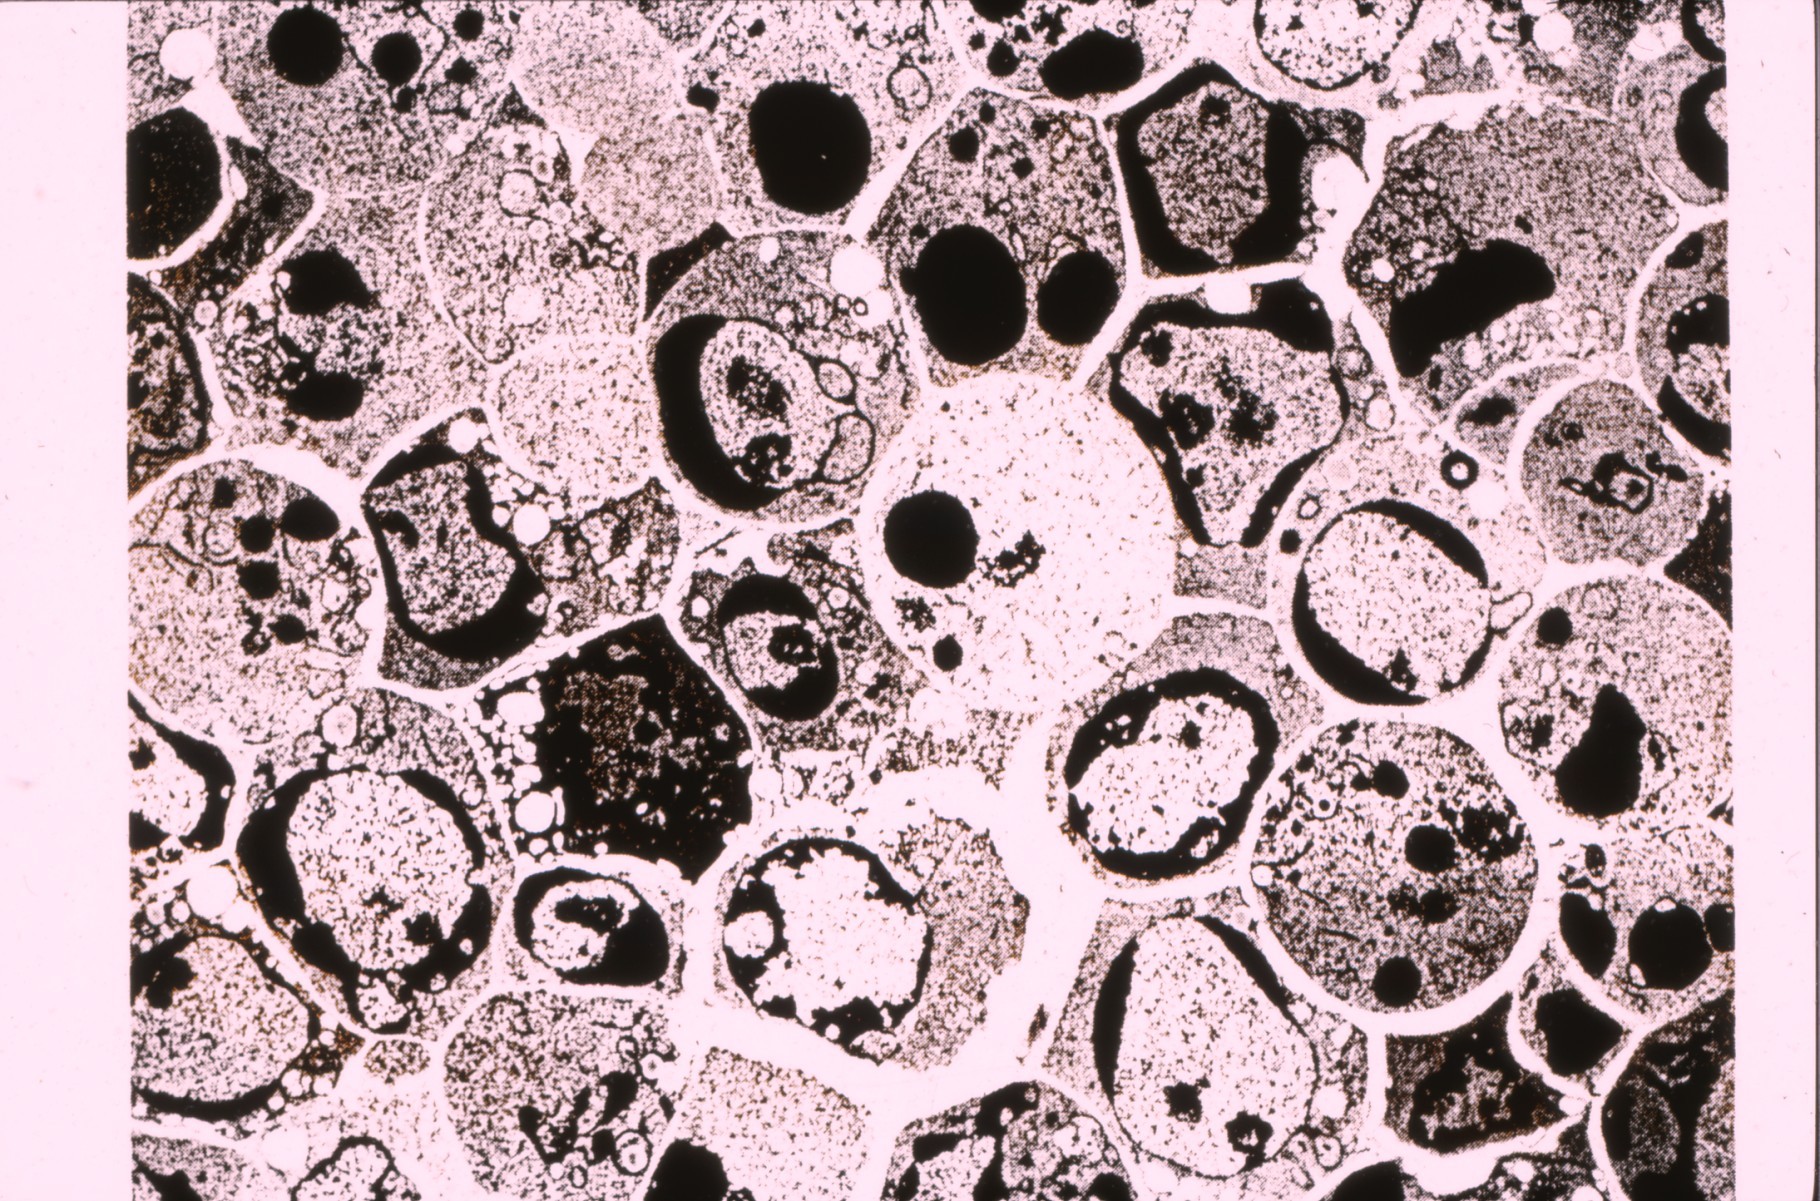

Image (36. Cy ablated follicles, residual cells)

36._CY_bursal_follicles Available under License Creative Commons Attribution. Download (1MB) |

Reconstitution of cyclophosphamide depleted bursal follicles and effects of constitutive over expression of Myc and other transgenes in chickens. Images from “An atlas of normal and Myc-induced neoplastic development in the bursa of fabricius.” Access the full Atlas at http://authors.fhcrc.org/368